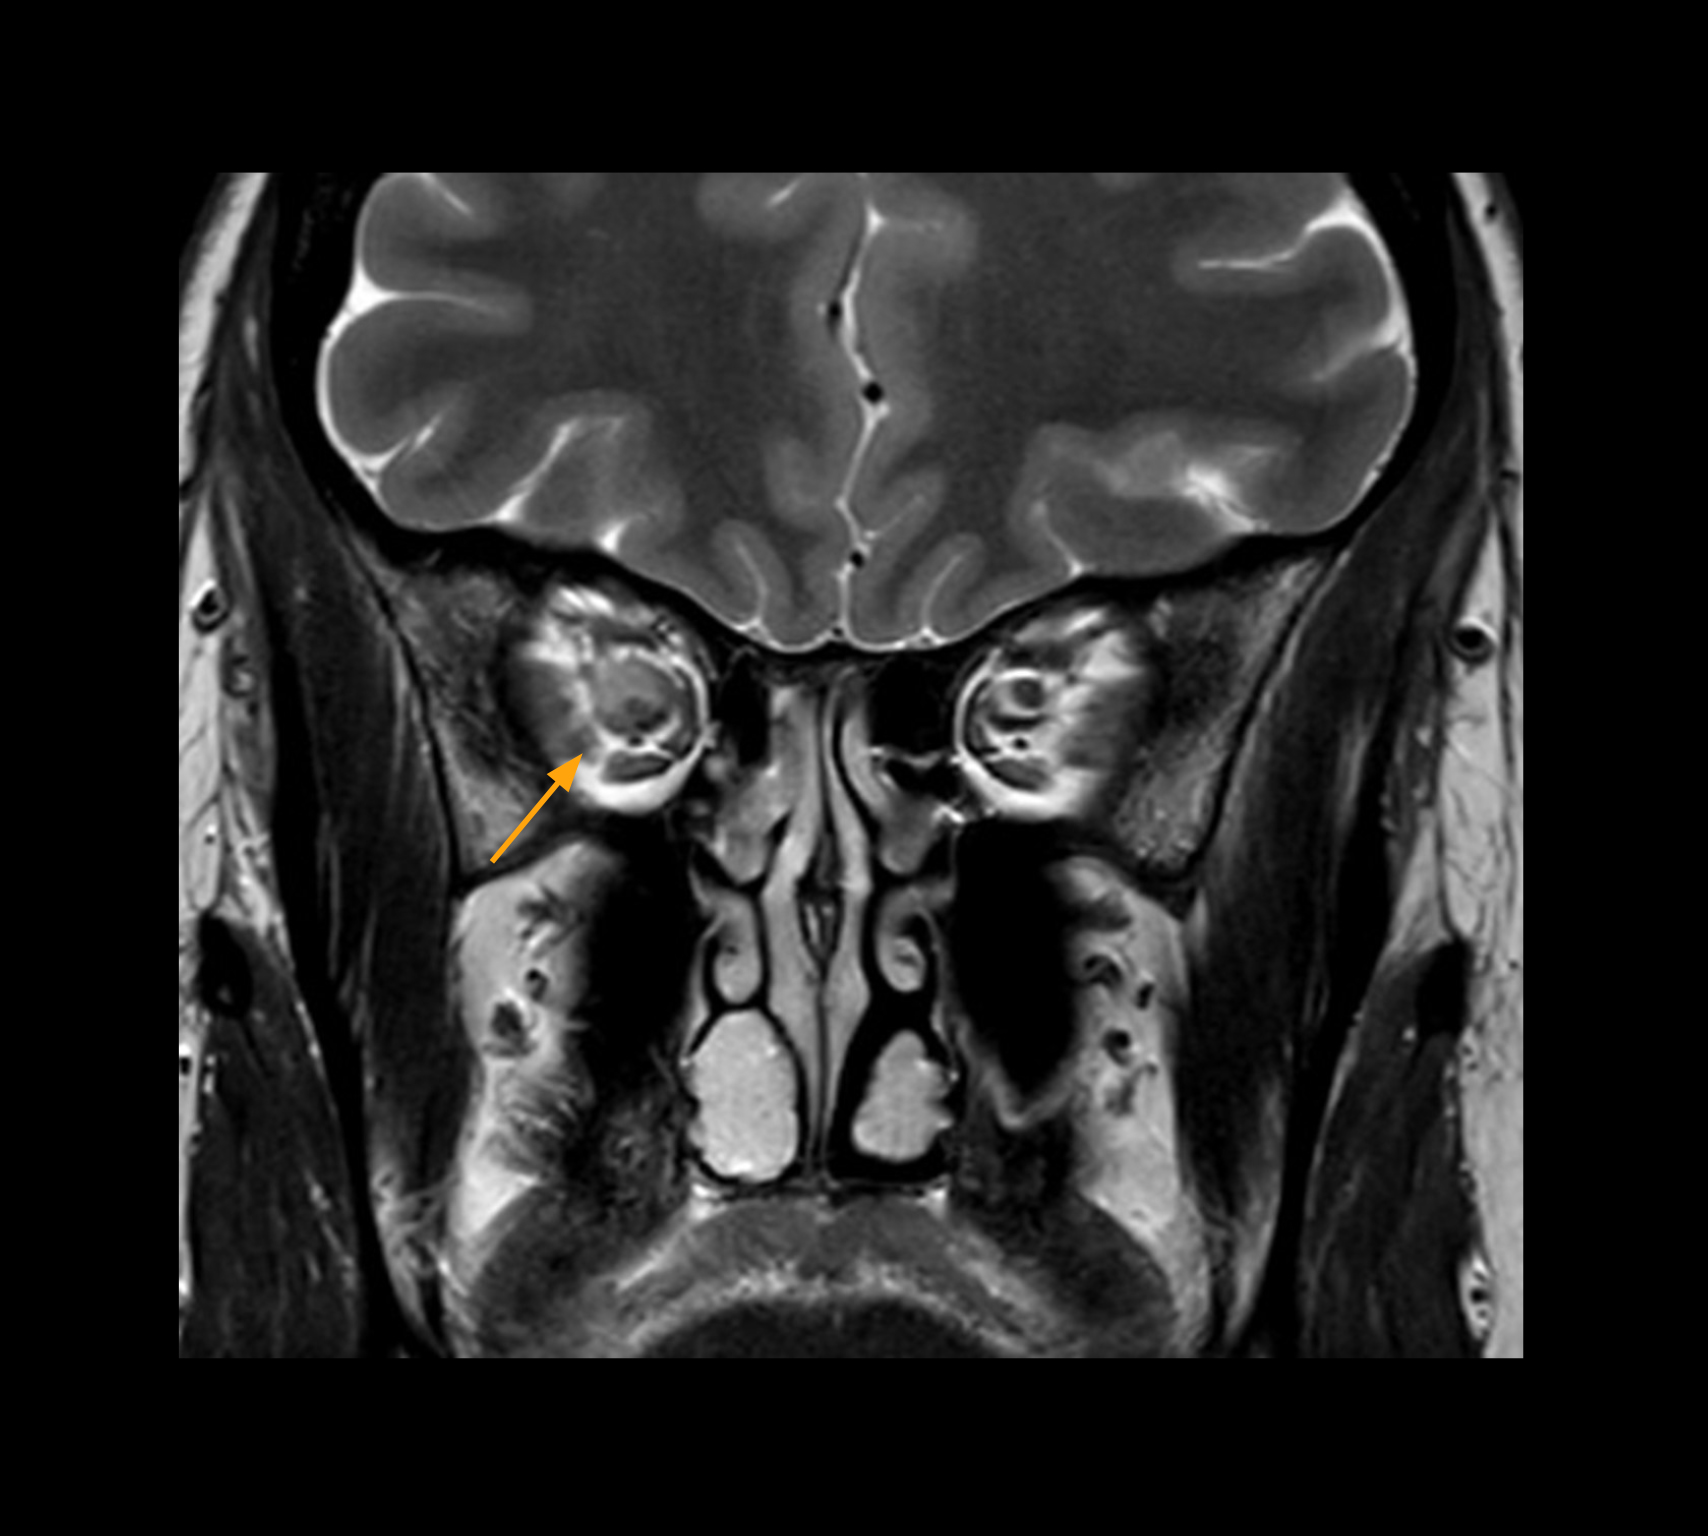

Imaging of the optic nerve sheath

High-resolution MRI impressively demonstrates the compression and narrowing of the right optic nerve in this case of optic nerve sheath meningioma (ONSM). The coronal T2-weighted images show the hyper-intense, half-moon shaped lesion, that is clearly visible in the axial T1W image after contrast injection (right). These imaging findings were so convincing that there sponsible neurosurgeon did not consider a pretherapeutic histological clarification.

High resolution-MRI impressively demonstrates the compression and narrowing of the right optic nerve in this case of optic nerve sheath meningioma (ONSM). The coronal T2-weighted images show the hyper-intense, half-moon shaped lesion, that is clearly visible in the axial T1W image after contrast injection (right). These imaging findings were so convincing that there sponsible neurosurgeon did not consider a pretherapeutic histological clarification.

High resolution providing diagnostic confidence

In select cases, the MR 7700 has helped the hospital’s physicians more clearly visualize pathology. “We’re definitely getting the impression that tumors are better delineated with the MR7700,” Dr. Heindel says. “For example, I examined a patient who had been diagnosed in another hospital with possible neuritis of the optic nerve. However, the MR 7700 images allowed me to diagnose it as an optic nerve sheath meningioma, a rare and often misdiagnosed, slowly growing tumor that wascausing the visual disturbances in the patient. The lesion was so well delineated on the high resolution MR 7700 images that our neurosurgeon decided he did not need a biopsy before proceeding directly with decompression of the optic canal and peeling away those tumor cells.”